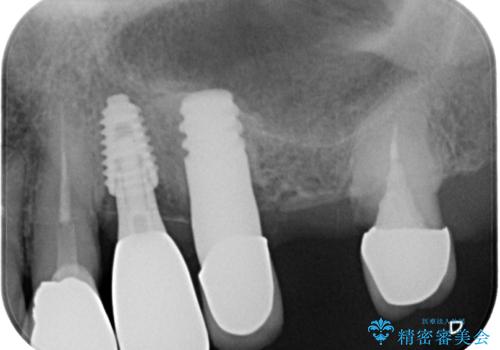

歯がボロボロで抜歯が必要な状態であり、後方にはインプラントが埋入されているため、同様にインプラントによる補綴治療を行うこととしました。

プラスチックを外すと同時に抜歯を行い、1ヶ月ほど待機して歯肉が落ち着いたことを確認してから速やかにインプラントを埋入することとしました。

従来は4ヶ月ほど待機してからの埋入が一般的でしたが、歯肉の炎症が落ち着いた時点で速やかに埋入できるようになり、4ヶ月の短期間で治療を終えることができました。